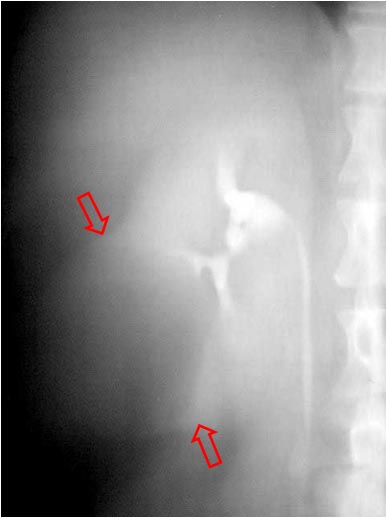

SIGNO DEL CHORRO O JET URETERAL INVERTIDO

Signo de crecimiento prostático en la fase excretora precoz de la urografía intravenosa. El crecimiento prostático provoca el levantamiento de los orificios de entrada de los uréteres a la vejiga y hace que el jet ureteral sea dirigido hacia arriba en vez de hacia abajo.

En la imagen vemos una gran hipertrofia prostática que levanta el suelo vesical (flecha negra) y altera la entrada de ambos uréteres (flechas rojas), si bien no vemos el jet.